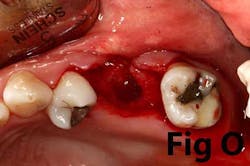

There is an abundance of literature showing increased gingival inflammation around natural dentition (exacerbated when a fixed restoration is present) when there is less than 2 mm AG. (Figs. 8, 9: post grafting) There is an abundance of literature showing increased incidence of peri-implant mucositis when there is inadequate attached tissue — a weaker connective tissue adhesion and lack of Sharpey’s fibers make the peri-implant tissue even more susceptible to bacterial challenge. (1-6, 8, 10) And as periodontitis is always preceded by gingivitis, peri-implantitis will be preceded by peri-implant mucositis. If we can decrease the incidence of peri-implant mucositis by providing a better and more resilient tissue phenotype, we can lower the incidence of peri-implantitis.The FGG procedure is indicated in cases of implant therapy where this is less than 2 mm of attached tissue present. Sometimes, a FGG is preferred over CTG because: (1) the FGG results in greater gain of attached tissue, (2) the FGG alleviates frenum/muscular pull whereas the connective tissue may increase muscular tension after the flap is coronally advanced, and (3) creeping attachment is often a positive byproduct of the FGG procedure.

Refer to Case Nos. 1 & 2.

Case No. 2